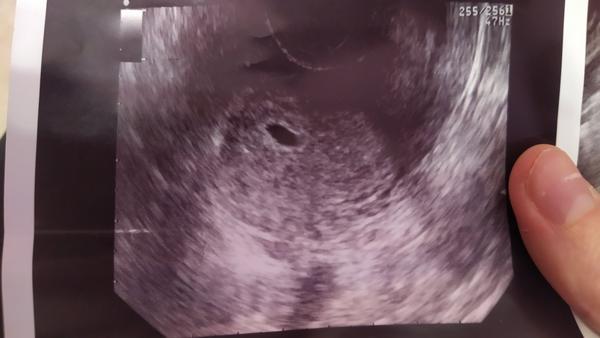

Prosím váš názor - 2 dutinky na sone

Ahojte. Chcela by som vediet váš názor. Prvé sono urobeny 28.4. a druhý dnes 7.5... 28.4.som mala len jednu dutinku a dnes už 2.. plod bohužiaľ nie je prítomný len váčok, podľa vás je možné že v druhej sa ešte objaví plod? Podľa doktora 100% že nie a podla neho mám ísť urgentne v pondelok na kyret,ale ja by som ešte chcela počkať, ale on o tom nechce ani počuť...Podla poslednej MS mám 8+3tt ale mám veľmi nepravidelný dlhší cyklus takže nedá sa určiť presne. Ďakujem za každý názor 🙏

Žienky , a prosím neviete že ako je to možné ze od minulého týždňa sa mi vytvorila ešte jedna dutinka (a je už väčšia ako tá prva) ? Lekár na to povedal že on to nevie, a nemám to riešiť keďže tam nepočuje srdiečko...